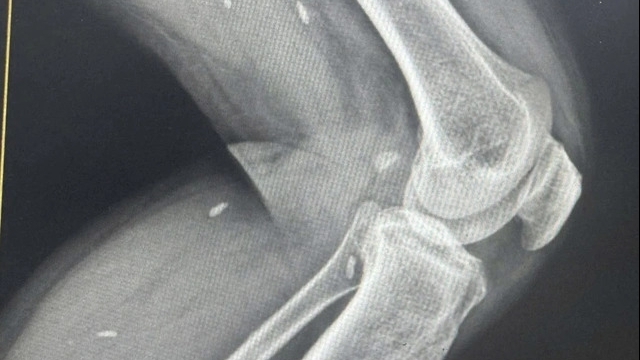

Tại Bệnh viện dã chiến số 1 - Trung tâm Y tế TP. Chí Linh, các bác sĩ đang theo dõi 20 ca có tổn thương ở phổi. Tuy nhiên, các bệnh nhân hiện chưa có triệu chứng quá nặng. Bệnh viện đang tiếp tục theo dõi chặt chẽ những trường hợp này để điều trị kịp thời theo đúng phác đồ, hạn chế diễn biến nặng.